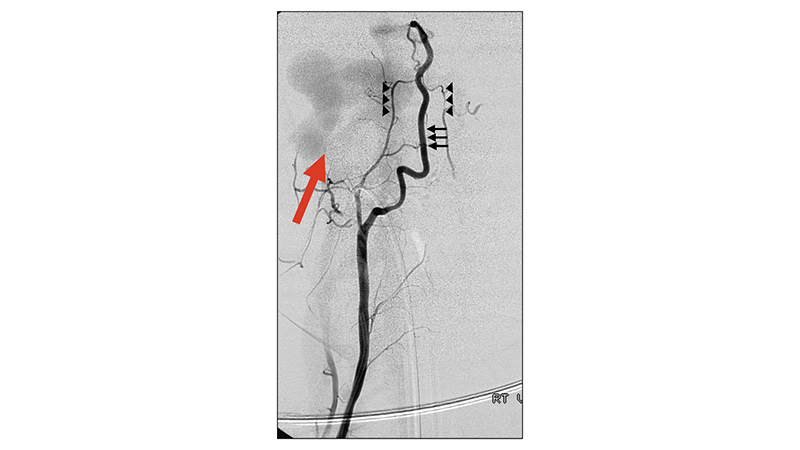

- Εκλεκτική αγγειογραφία της δεξιάς σπονδυλικής αρτηρίας σε προσθιοπίσθια λήψη. Η δεξιά σπονδυλική αρτηρία είναι υποπλαστική. Διακρίνουμε το αρτηριακό τόξο του οδόντα του Α2 σπονδύλου (αιχμές μαύρων βελών) και ευμεγέθη ριζομυελική αρτηρία που αιματώνει την προσθία νωτιαία αρτηρία στο ύψος του αυχενικού μυελού (μαύρα βέλη). Από την προσθία νωτιαία αρτηρία διά της σπονδυλοβασικής συμβολής, με αναστροφή στην δεξιά σπονδυλική αρτηρία μέχρι το Α2 τμήμα, σκιαγραφείται η επικοινωνία (κόκκινο βέλος).